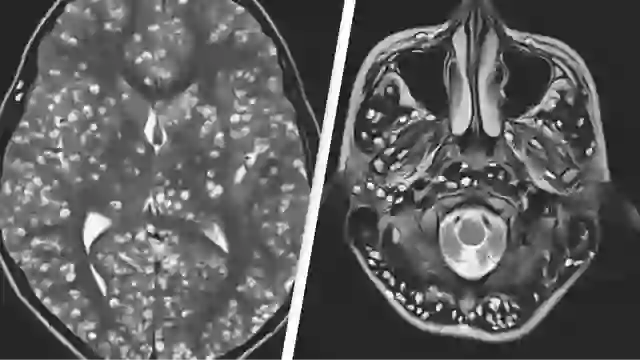

In a paper published in PLoS Pathogens, scientists explained how the parasite can interfere with brain cells by infecting a number of neurons.

The neurons impacted by the toxin were found to release fewer extracellular vesicles which are crucial in exchanging information.

Using a combination of mice and human cells, Wilson explained the research revealed how the disruption of neurons can result in heightened glutamate levels, leading to seizures and other neurological issues.